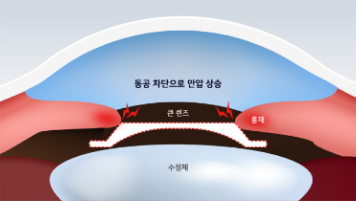

렌즈 사이즈로 볼팅을 높여서 회전 가능한 공간을 줄입니다.

이는 눈 속에 렌즈가 끼어 회전을 못하도록 하는 방법으로

시간이 지난 후 안구 내 안압 상승 및 녹내장의

부작용이 발생할 수 있습니다.

수평으로 렌즈를 삽입할 경우 렌즈 움직임을 최소화하기 위해 눈 보다 큰 사이즈의 렌즈를 삽입하게 되는데 이는 안압 상승의 문제점과 백내장과 녹내장과 같은 치명적인 부작용이 발생할 수 있습니다.

큰 렌즈를 삽입할 경우

Low 볼팅에서도

낮은 렌즈 회전 가능성

렌즈회전 방지를 위해 high 볼팅의 관례이나, V-토릭 ICL은

렌즈회전 방지를 위해 high 볼팅의 관례이나, V-토릭 ICL은

Low 볼팅에도 낮은 렌즈 회전 가능성을 보이며,

볼팅을 높여서 발생하는 부작용을 예방할 수 있다.